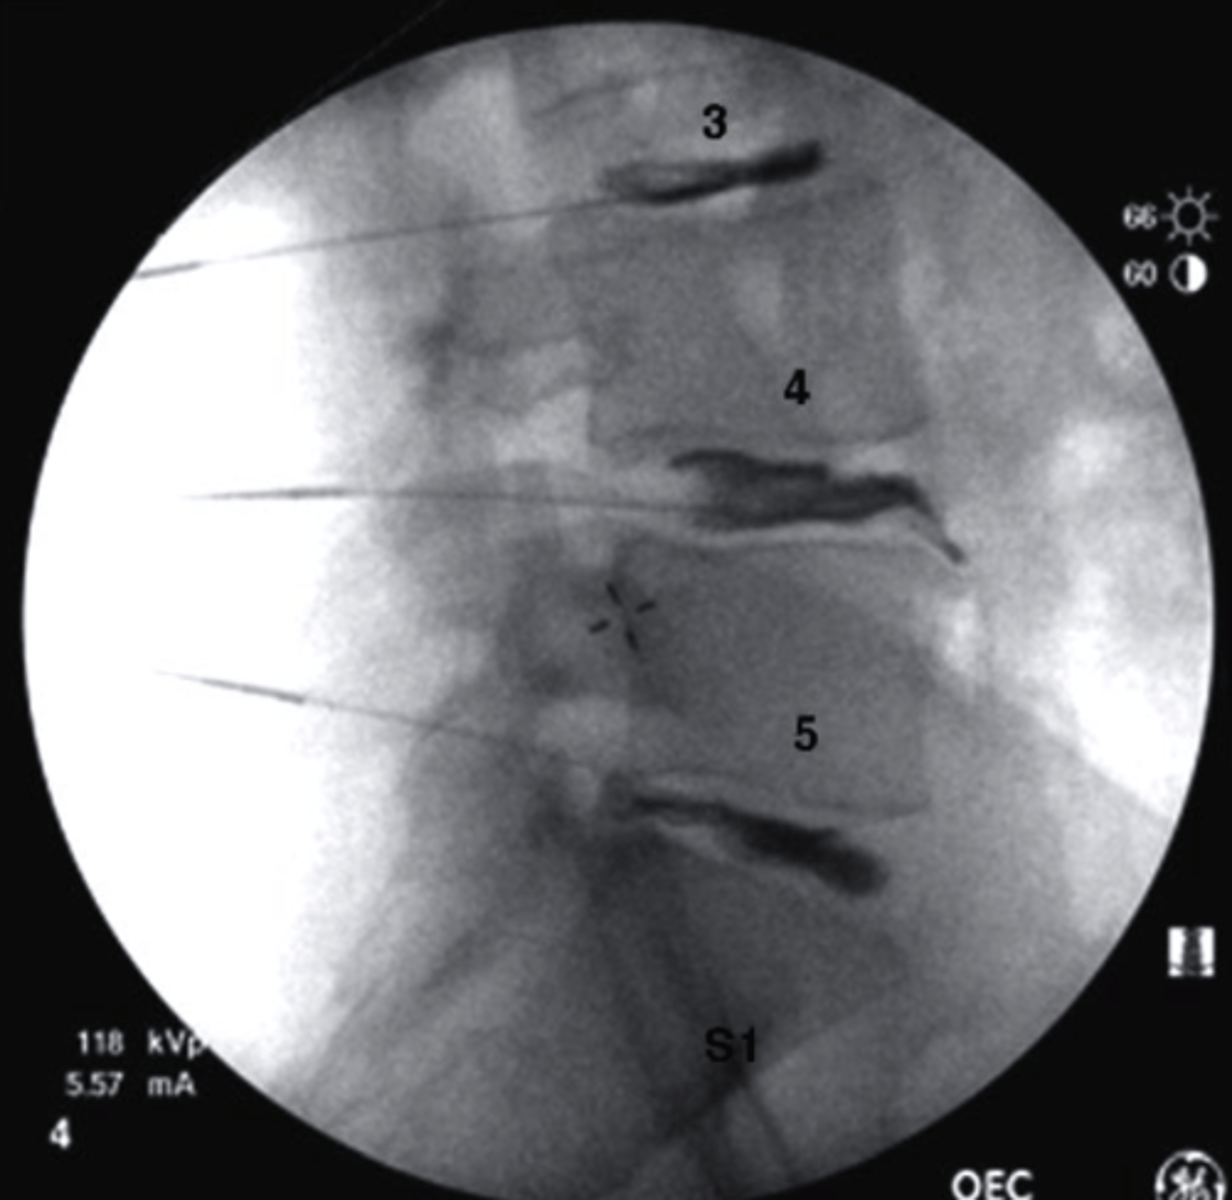

what is fluoroscopy

Fluoroscopy

What type of imaging study is this?

a. PET scan

b. Bone Scan

c. T1 MRI

d. Fluoroscopy